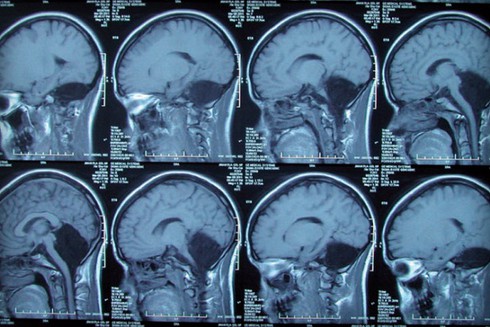

Sự việc chỉ được phát hiện khi cô gái trẻ đến khám tại bệnh viện PLA General (Trung Quốc) do bị chóng mặt. Sau khi xem ảnh chụp X-quang, các bác sỹ cho biết não của cô gái thiếu một thành phần rất quan trọng liên quan đến việc điều khiển hành vi là tiểu não.

Tiểu não là một bộ phận nằm phía sau hộp sọ. Tuy được gọi là "tiểu não" nhưng thực tế thì nó chứa đến 50% tế bào thần kinh của bộ não.

Các bác sỹ cũng rất ngạc nhiên là tại phần tiểu não bị khuyết lại chứa dịch tủy não. Điều này có thể khiến cô gái trẻ sống khó khăn đến hết cuộc đời. Thực tế, đây cũng chính là lý do khiến cô gái đến 6 tuổi mới biết nói, và 7 tuổi mới tự đi lại được. Hơn nữa, cô cũng thường gặp khó khăn trong việc duy trì thăng bằng và điều này đã ảnh hưởng đến hầu hết các hoạt động trong cuộc sống hàng ngày của cô.